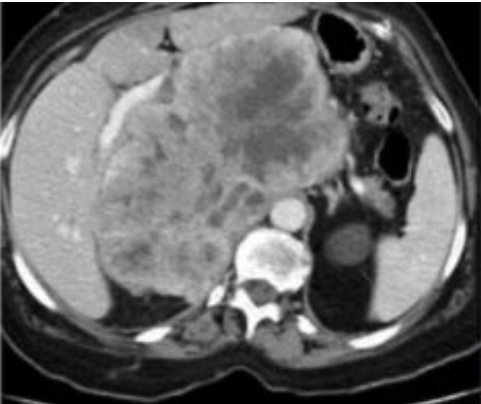

TOMOGRAFIA DE ABDOMEN COM CONSTRASTE VENOSO .

MASSA RETROPERITONEAL A DIREITA QUE COMPRIME AS VISCERAS A DIREITA , A QUAL NÃO INVADE AS ESTRUTURAS. PRESENÇA DE CAPTAÇÃO HETEROGENEA DO CONSTRASTE NA PERIFERIA

ASPECTO DE SARCOMA PERITONEAL.